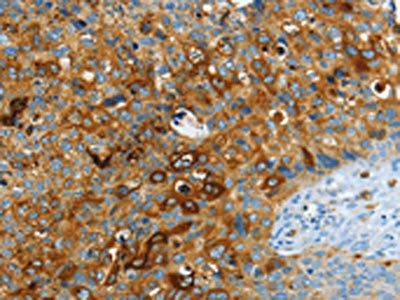

The image on the left is immunohistochemistry of paraffin-embedded Human cervical cancer tissue using CSB-PA208943(ASAH1 Antibody) at dilution 1/40, on the right is treated with fusion protein. (Original magnification: ×200)

The image on the left is immunohistochemistry of paraffin-embedded Human breast cancer tissue using CSB-PA208943(ASAH1 Antibody) at dilution 1/40, on the right is treated with fusion protein. (Original magnification: ×200)